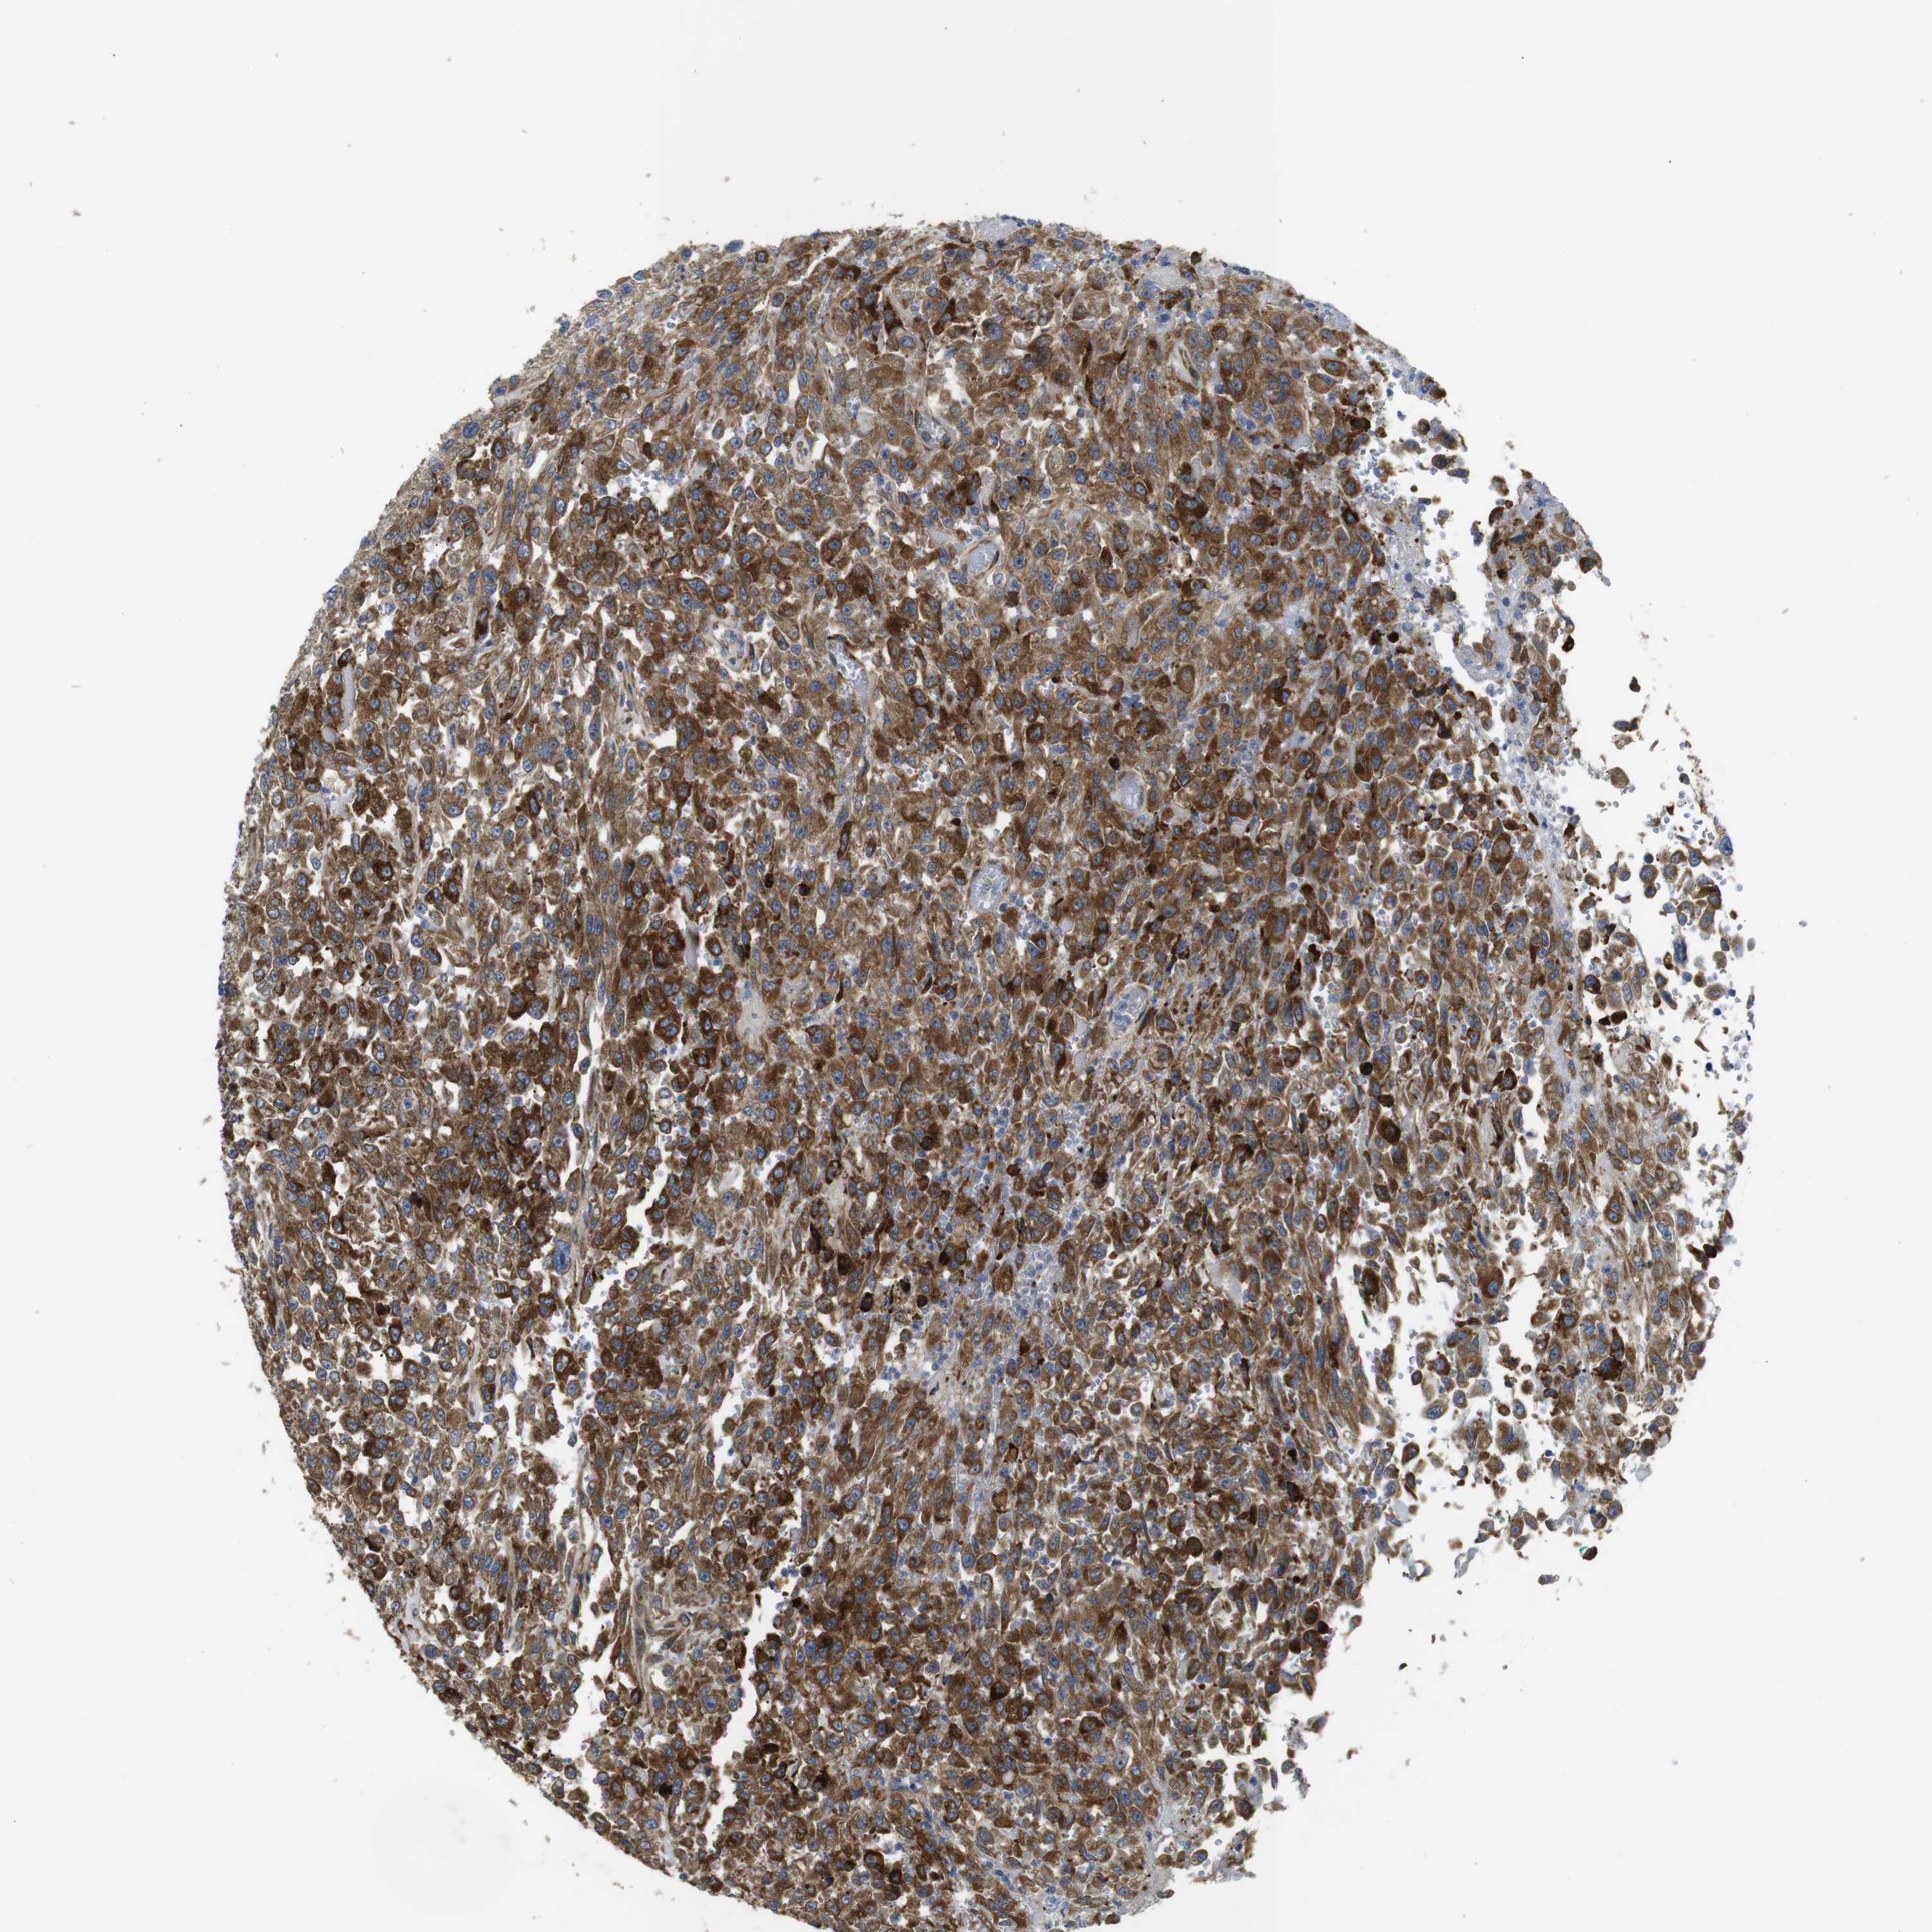

UROTHELIAL CANCER - Protein expressioni

A mouse-over function shows sample information and annotation data. Click on an image to view it in a full screen mode. Samples can be filtered based on level of antibody staining by selecting one or several of the following categories: high, medium, low and not detected. The assay and annotation is described here.

Note that samples used for immunohistochemistry by the Human Protein Atlas do not correspond to samples in the TCGA dataset.

Antibody stainingi

Antibody staining in the annotated cell types in the current human tissue is reported as not detected, low, medium, or high, based on conventional immunohistochemistry profiling in selected tissues. This score is based on the combination of the staining intensity and fraction of stained cells.

Each image is clickable and will lead to virtual microscopy that enables deeper exploration of all samples and also displays staining intensity scores, fraction scores and subcellular localization as well as patient and tissue information for each sample.

Antibody HPA003332

Staining

High

Medium

Low

Not detected

Intensity

Strong

Moderate

Weak

Negative

Quantity

>75%

75%-25%

<25%

None

Location

Nuclear

Cytoplasmic/membranous

Cytoplasmic/membranous,nuclear

Urothelial carcinoma, Low grade

Urothelial carcinoma, High grade